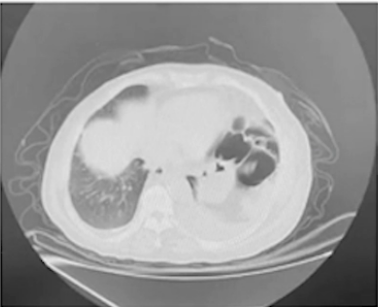

2024-5-13 妇科彩超:宫颈大小正常,双卵巢未探及,盆腹腔巨大囊实性肿物28cm×35cm×17.7cm,内壁不平,实性突起直径5.4cm,内有分隔,厚约0.6cm。

2024-5-26 MR增强:腹盆腔巨大囊性信号灶,最大横截面大小约27.5cm×17.7cm,其内局部多发乳头状突起,最大截面3.3cm×2.8cm,无明显强化,考虑残存附件上皮来源可能。